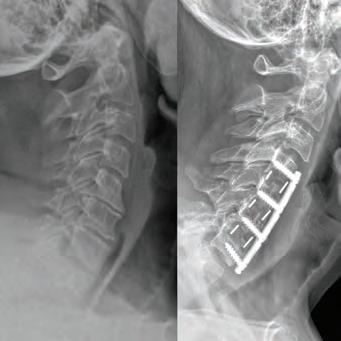

SURGERY: C4/C5, C5/C6, C6/C7 ACF (ANTERIOR CERVICAL FUSION)

“Great medicine coupled with great care. Dr. Courtney takes the time to listen to your medical needs. He put me at ease regarding my condition.”